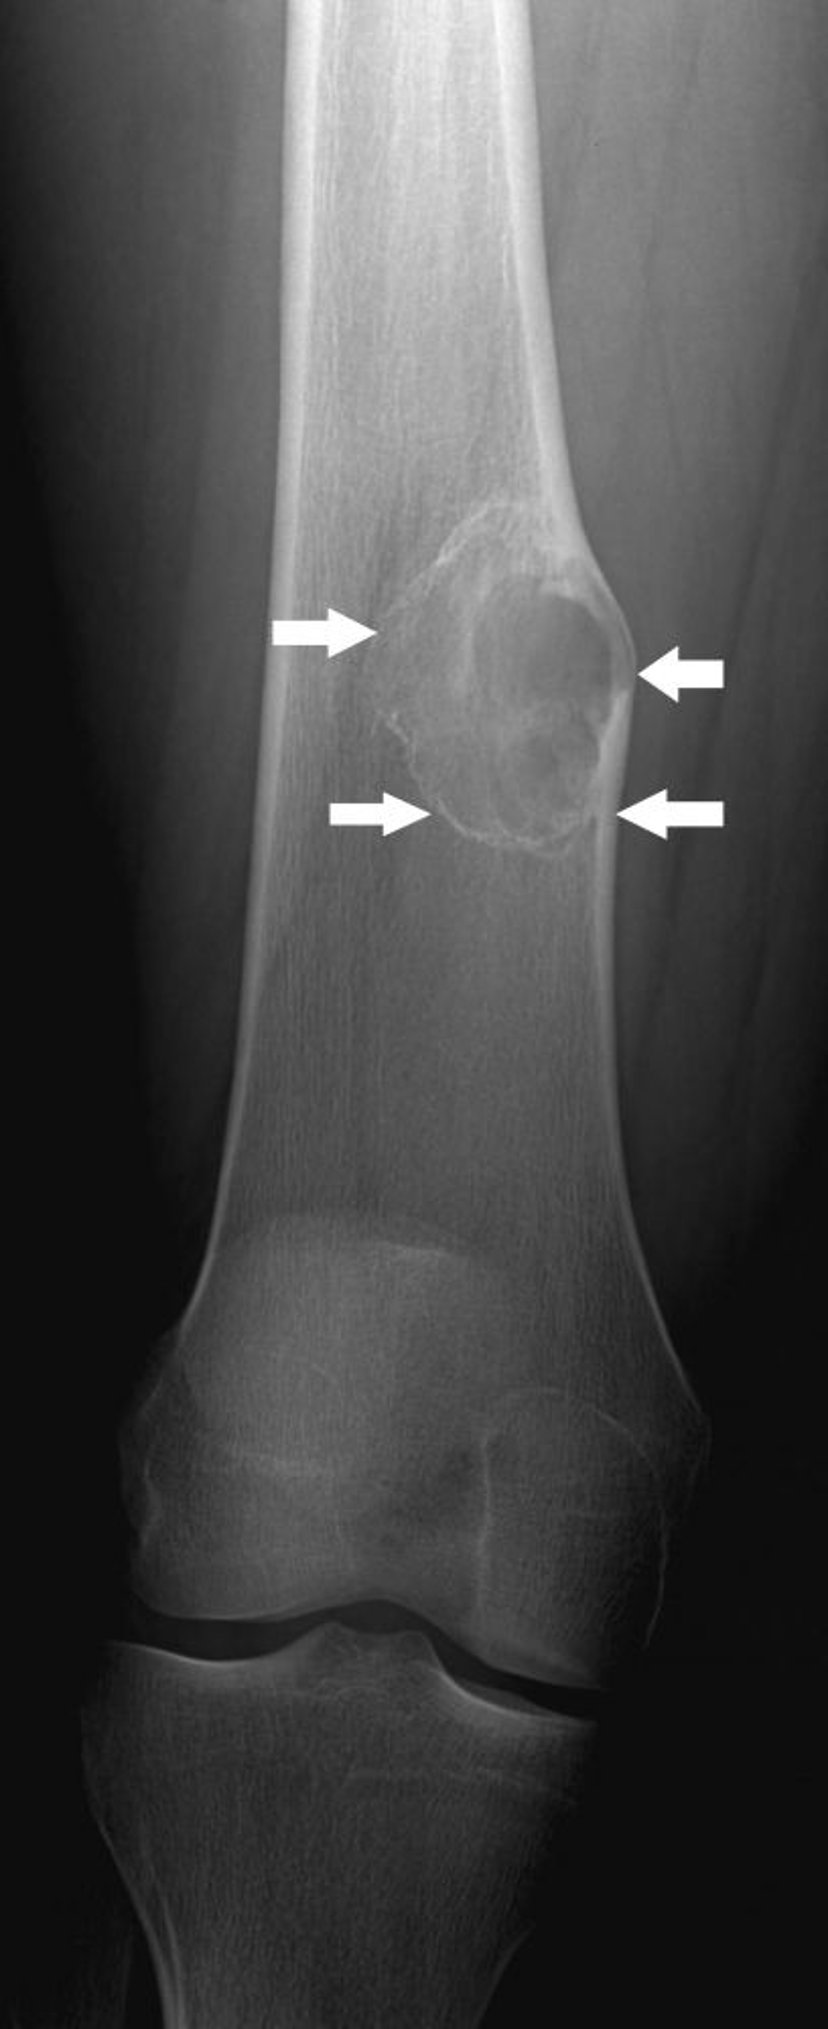

Неоссифицирующая фиброма

На данном рентгеновском снимке показано костное поражение (стрелки) выше колена в бедренной кости с умеренным расширением, что характерно для неоссифицирующей фибромы.

Image courtesy of Michael J. Joyce, MD, and Hakan Ilaslan, MD.